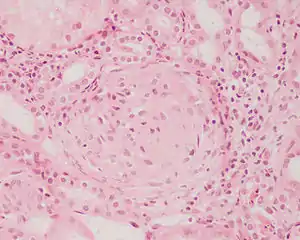

| Photomicrograph of a kidney biopsy from a person with crescentic glomerulonephritis showing prominent fibrocellular crescent formation and moderate mesangial proliferation in a glomerulus. Hematoxylin and eosin stain. | |

Rapidly progressive glomerulonephritis, also known as crescentic GN, is characterised by a rapid, progressive deterioration in kidney function. People with rapidly progressive glomerulonephritis may present with a nephritic syndrome. In management, steroid therapy is sometimes used, although the prognosis remains poor.[8] Three main subtypes are recognised:[4]:557–558

Histopathologically, the majority of glomeruli present "crescents". Formation of crescents is initiated by passage of fibrin into the Bowman space as a result of increased permeability of glomerular basement membrane. Fibrin stimulates the proliferation of endothelial cells of Bowman capsule, and an influx of monocytes. Rapid growing and fibrosis of crescents compresses the capillary loops and decreases the Bowman space, which leads to kidney failure within weeks or months.